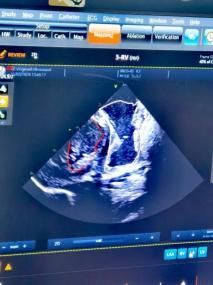

動物實驗選用中型體重的豬,導管由穿刺頸靜脈至上腔靜脈進入心臟,無需動刀。建立入路后,先在心腔內(nèi)超聲指導下,完成心臟內(nèi)部結(jié)構(gòu)的電學重構(gòu),標記出希氏束、左右束支等心臟傳導束的位置,走行路線,以希氏束導管為路標,指導無導線起搏器的植入。無導線起搏器到位后,由心腔內(nèi)超聲成像確認起搏器固定于心臟間隔,測試起搏參數(shù)。

圖5.心腔內(nèi)超聲成像,確認無導線起搏器掛靠間隔的位置。